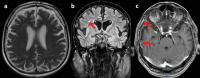

Post-acute COVID-19 syndrome presented as a cerebral and systemic vasculitis: a case report